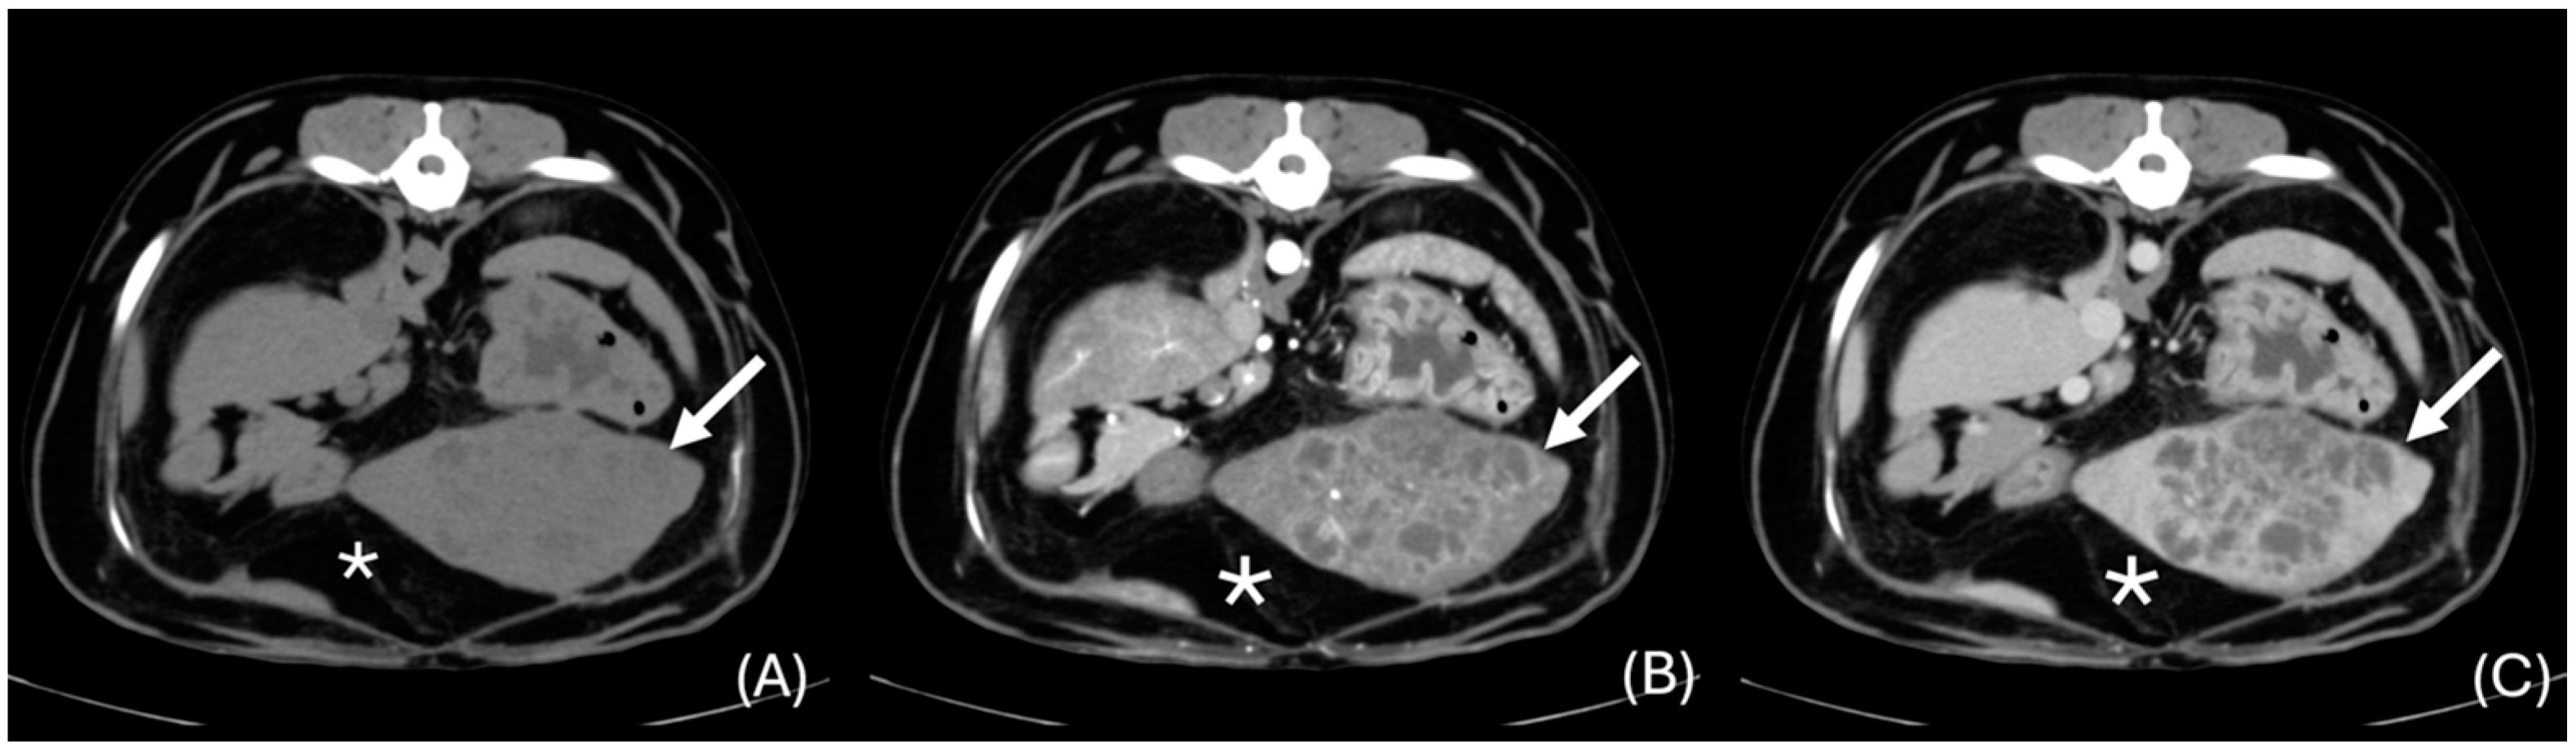

3.6.2. “Discrete” Changes